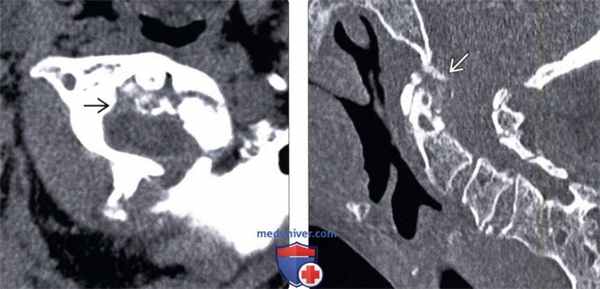

(Слева) КТ, аксиальный срез: распространенная аморфная кальцификация ретродентальных мягких тканей с умеренным объемным воздействием на вентральную поверхность дурального мешка. Подобная картина может никак не проявлять себя клинически, однако также может сопровождаться симптомами воспалительного или объемного процесса.

(Справа) КТ, сагиттальный срез: у пациента с болезнью накопления пирофосфата кальция определяется нечетко ограниченная кальцификация тканей позади зубовидного отростка. Обратите внимание на дегенеративные кистозные изменения зубовидного отростка и сужение суставной щели атлантодентального сустава.